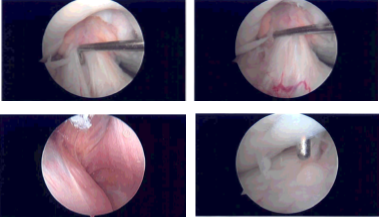

The medical entry was made with the use of a spinal needle and blade. Examination of the medial tibiofemoral compartment showed intact cartilage and meniscus. Examination of the intercondylar notch showed intact, but frayed and degenerated ACL. There was a tear flap from the anterior margin of the lateral meniscus.

A shaver was used to debride the meniscus and do the meniscectomy. Examination of the rest of the lateral tibiofemoral compartment showed intact cartilage of meniscus. Examination of the patellofemoral compartment showed grade 1 changes over the trochlea and patella.

There was a grade 2 osteochondral lesion of the patella, which was debrided with the use of a shaver. The rest of the knee was intact. The knee was thoroughly irrigated and drained. All the pictures were saved.

Intraoperative Arthroscopy Images